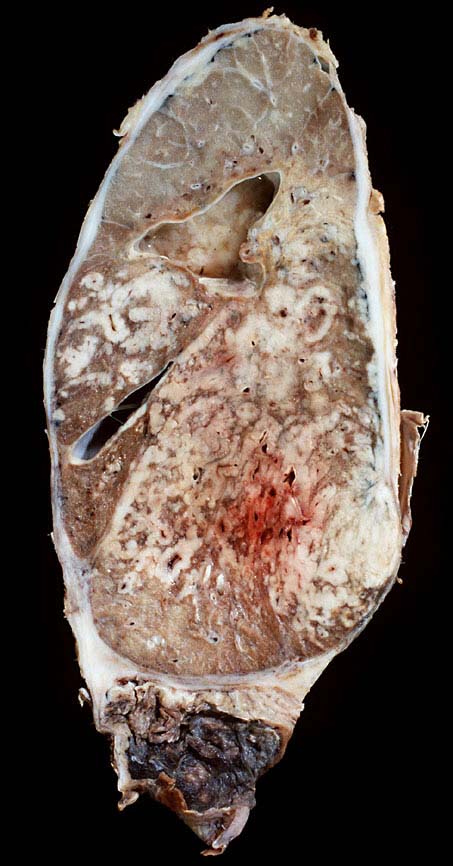

Das metastatische Wachstumsmuster von primären Bronchuskarzinomen und extrapulmonalen Tumoren innerhalb der Lunge ist variabel. Hämatogene Metastasen imponieren makroskopisch als multiple scharf begrenzte rundliche Knoten in allen Lappen meist in peripherer Lage. Der metastatische Befall von Lymphknoten kann durch direkte Tumorinfiltration durch den Primärtumor erfolgen (=per continuitatem) oder über die Lymphgefässe. Bei einer ausgeprägten lymphogenen Tumorausbreitung erscheinen subpleurale mit Tumor gefüllte Lymphgefässe makroskopisch als prominente weisse Streifen. Mikroskopisch lassen sich Tumorinfiltrate in peribronchialen und perivaskulären Lymphgefässen nachweisen (=Lymphangiosis carcinomatosa). Hepatozelluläre Karzinome metastasieren typischerweise in Form von Tumorembolien (> 1279) hämatogen in die Lunge.

• Sternförmiges Karzinom mit zentraler Vernarbung mit reichlich schwarzem Anthrakosepigment.

• Peritumorales Lungenemphysem (Traktionsemphysem).